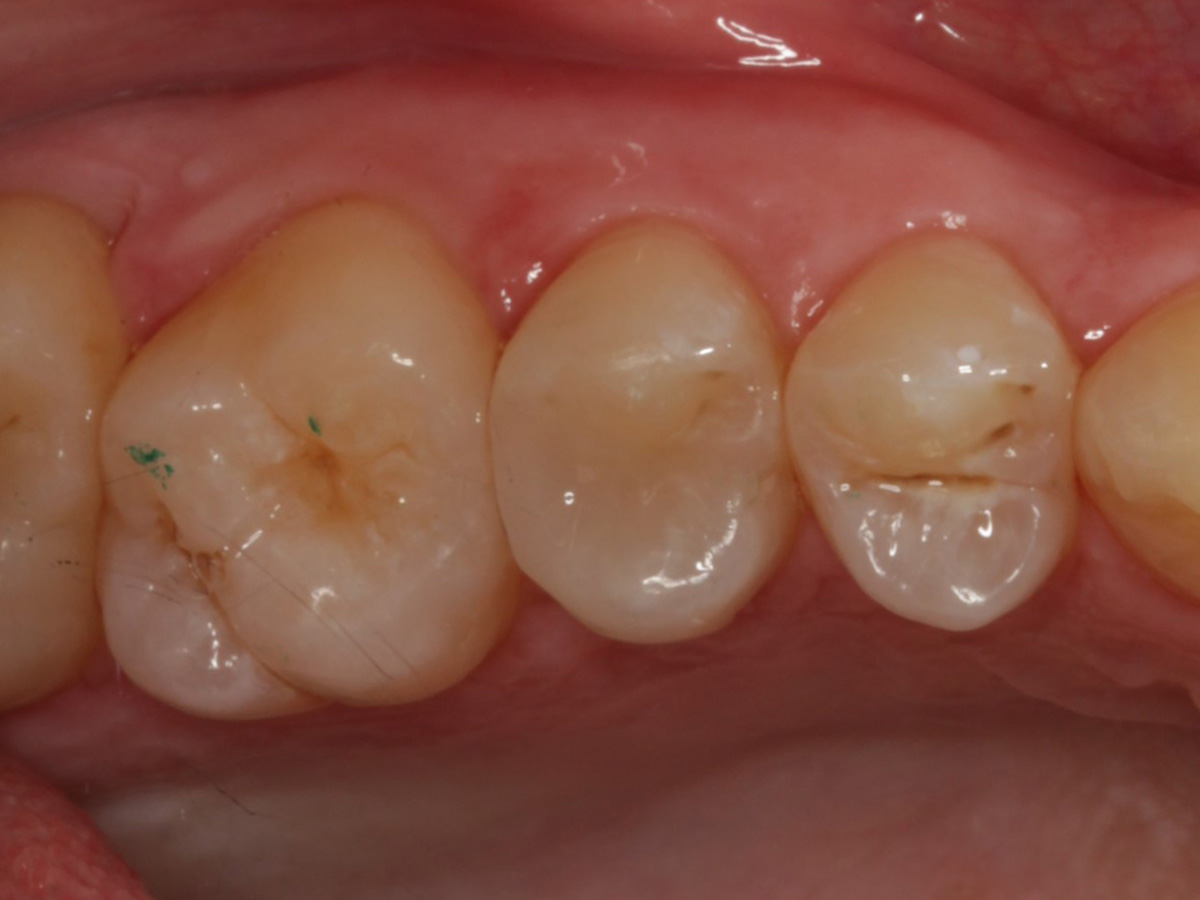

Abbildung 2

Bissflügelröntgenaufnahme